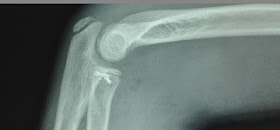

Lesión Salter-Harris II cabeza radial

Reducción abierta y osteosíntesis con tornillos canulados 2.0